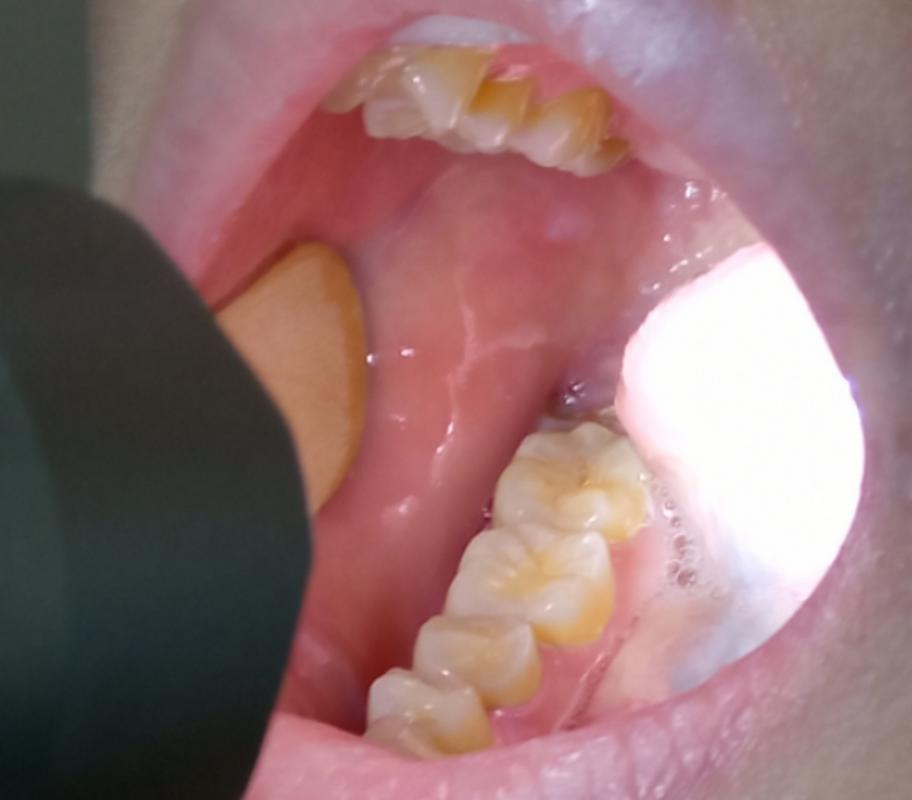

口腔白色黏膜是何原因?

为了帮助您更好地理解,我将这些原因分为三大类:生理性/良性、炎症性、癌前/恶性病变。

癌前病变或恶性病变(需要高度警惕并立即就医)

这类白色斑块通常是质地坚硬、不易擦除、长期不消且持续增大的。

白斑

- 表现:口腔黏膜上出现的不能被擦除的白色或灰白色斑块,质地较硬,表面可有皲裂或溃疡,无明显自觉症状,或仅有粗糙感。长期存在、持续增大的白斑,尤其是发生在舌缘、口底、颊黏膜等部位的,癌变风险较高。

- 原因:最主要的危险因素是吸烟(包括雪茄、烟斗)、嚼槟榔、酗酒。

- 处理:必须立即就医!医生会进行详细检查,必要时取一小块组织做病理活检(金标准),以排除癌前病变或口腔癌的可能性,治疗可能包括手术切除、药物等。